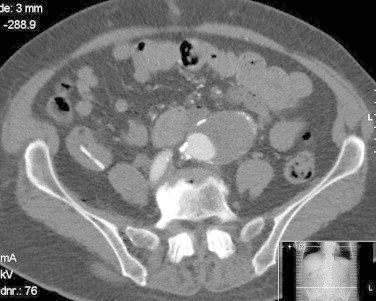

A 74-year-old woman, seen at another hospital for a 40 mm abdominal aortic aneurysm (AAA) one year earlier, presented to our vascular clinic. She complained of severe abdominal and back pain, which had lasted all day. Physical examination revealed a tender AAA. CT-angiography, demonstrated an infrarenal AAA with a diameter of 52 mm (Fig. 1, Fig. 4). Endovascular treatment with an Endurant® stentgraft was performed. Postoperatively, the patient initially was pain free. However, in the following days, she repeatedly experienced abdominal pain, now situated in the right lower quadrant. Review of the pre-operative CT-angiogram revealed a foreign body in the terminal ileum, which had been missed in the setting of a typical symptomatic AAA presentation. The patient could not remember having eaten anything unusual. During colonoscopy, the foreign body was seen inside the terminal ileum (Fig. 2, Fig. 5), and removal was attempted. Excessive pain was experienced during this attempt, raising concerns about possible perforation. Therefore, endoscopic retrieval was abandoned in favor of a laparotomy with enterotomy. In the terminal ileum, a plastic clip of the type normally used to close a bread bag was found (Fig. 6). The beak of the clip had attached itself to the mucosa of the small intestine (Fig. 3). Postoperatively, the patient had no abdominal complaints.

Fig. 4.

CT-image of AAA and foreign body.